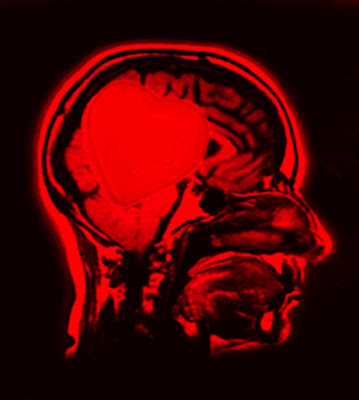

"Cuando nos enamoramos, en nuestro cerebro se activa una zona que produce dopamina, un estimulante natural del sistema nervioso que nos hace enfocarnos, mentalizarnos, tener más energía y movilizarnos hacia nuestro objetivo: la persona amada", explicó.

Dicha actividad es tan evidente que puede verse en un escáner cerebral.